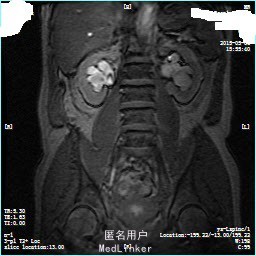

1. 2014.10腹部+盆腔CT增强:胰头部形态较小,未见明显异常密度灶,双侧腹股沟及后腹膜多发小淋巴结显示;肝脏及双肾多发小囊肿。 2. 2014.10超声胃镜提示:贲门粘膜隆起灶(息肉可能);病理提示浅表性粘膜慢性炎,活动期,HP(-)。PET/CT提示:胃角部壁厚稍僵硬伴代谢增高,建议行胃镜检查。左侧锁骨上淋巴结稍大伴代谢稍高,请结合临床。右肺中叶微小结节灶,代谢不高,随访,左肺下叶条索灶,肝多发小囊肿。右肾囊肿。全身PET/CT显像其余部位目前未见明显异常增高代谢病灶。 3. 2014.11.7前列腺MR增强:膀胱壁弥漫性不均匀增厚伴局部结节样改变,建议完善膀胱镜检查,前列腺稍饱满,请结合临床及超声检查,双侧腹股沟区多大淋巴结,部分增大,随访。 4. 2015.3.19B超提示双侧肾盂积水,左侧输尿管上段扩张,右侧输尿管上段轻度扩张,左肾结晶,膀胱壁局部增厚,前列腺轻度增生,残余尿27.61ml。 5. 膀胱镜:膀胱新生物:灰白半芝麻-芝麻大组织二块。病理提示(膀胱)印戒细胞癌,酶标示:CEA+,CK20-,CK7+,CK19-,Villin-,CEA+,P53+,P63-,ki67+80%。